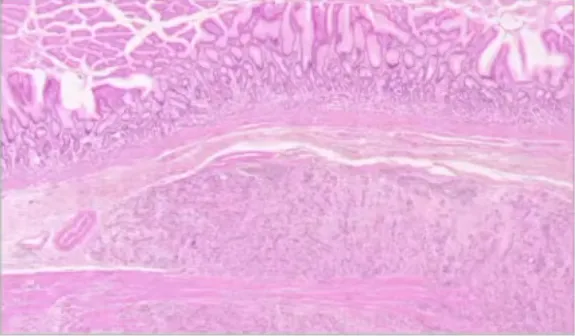

GLl1改变性肿瘤(含胃母细胞瘤)

• 定义:低级别双相上皮-间叶性肿瘤,包含胃母细胞瘤。

• 病因/发病机制:病因不明;以ACTB::GLI1融合最常见,其次为MALAT1:.GLI1等多种 GLI1融合。

• 病理

大体:胃壁肌层内分叶、结节状,质软,可伴出血。

镜下:典型双相(梭形细胞+上皮细胞),少数单相上皮型;核分裂、坏死少见。

• 免疫组化:梭形细胞CD10/CD56+;上皮细胞角蛋白+;肿瘤均可见GLI1核表达。

• 预后:病例少,总体惰性;手术切除为主。